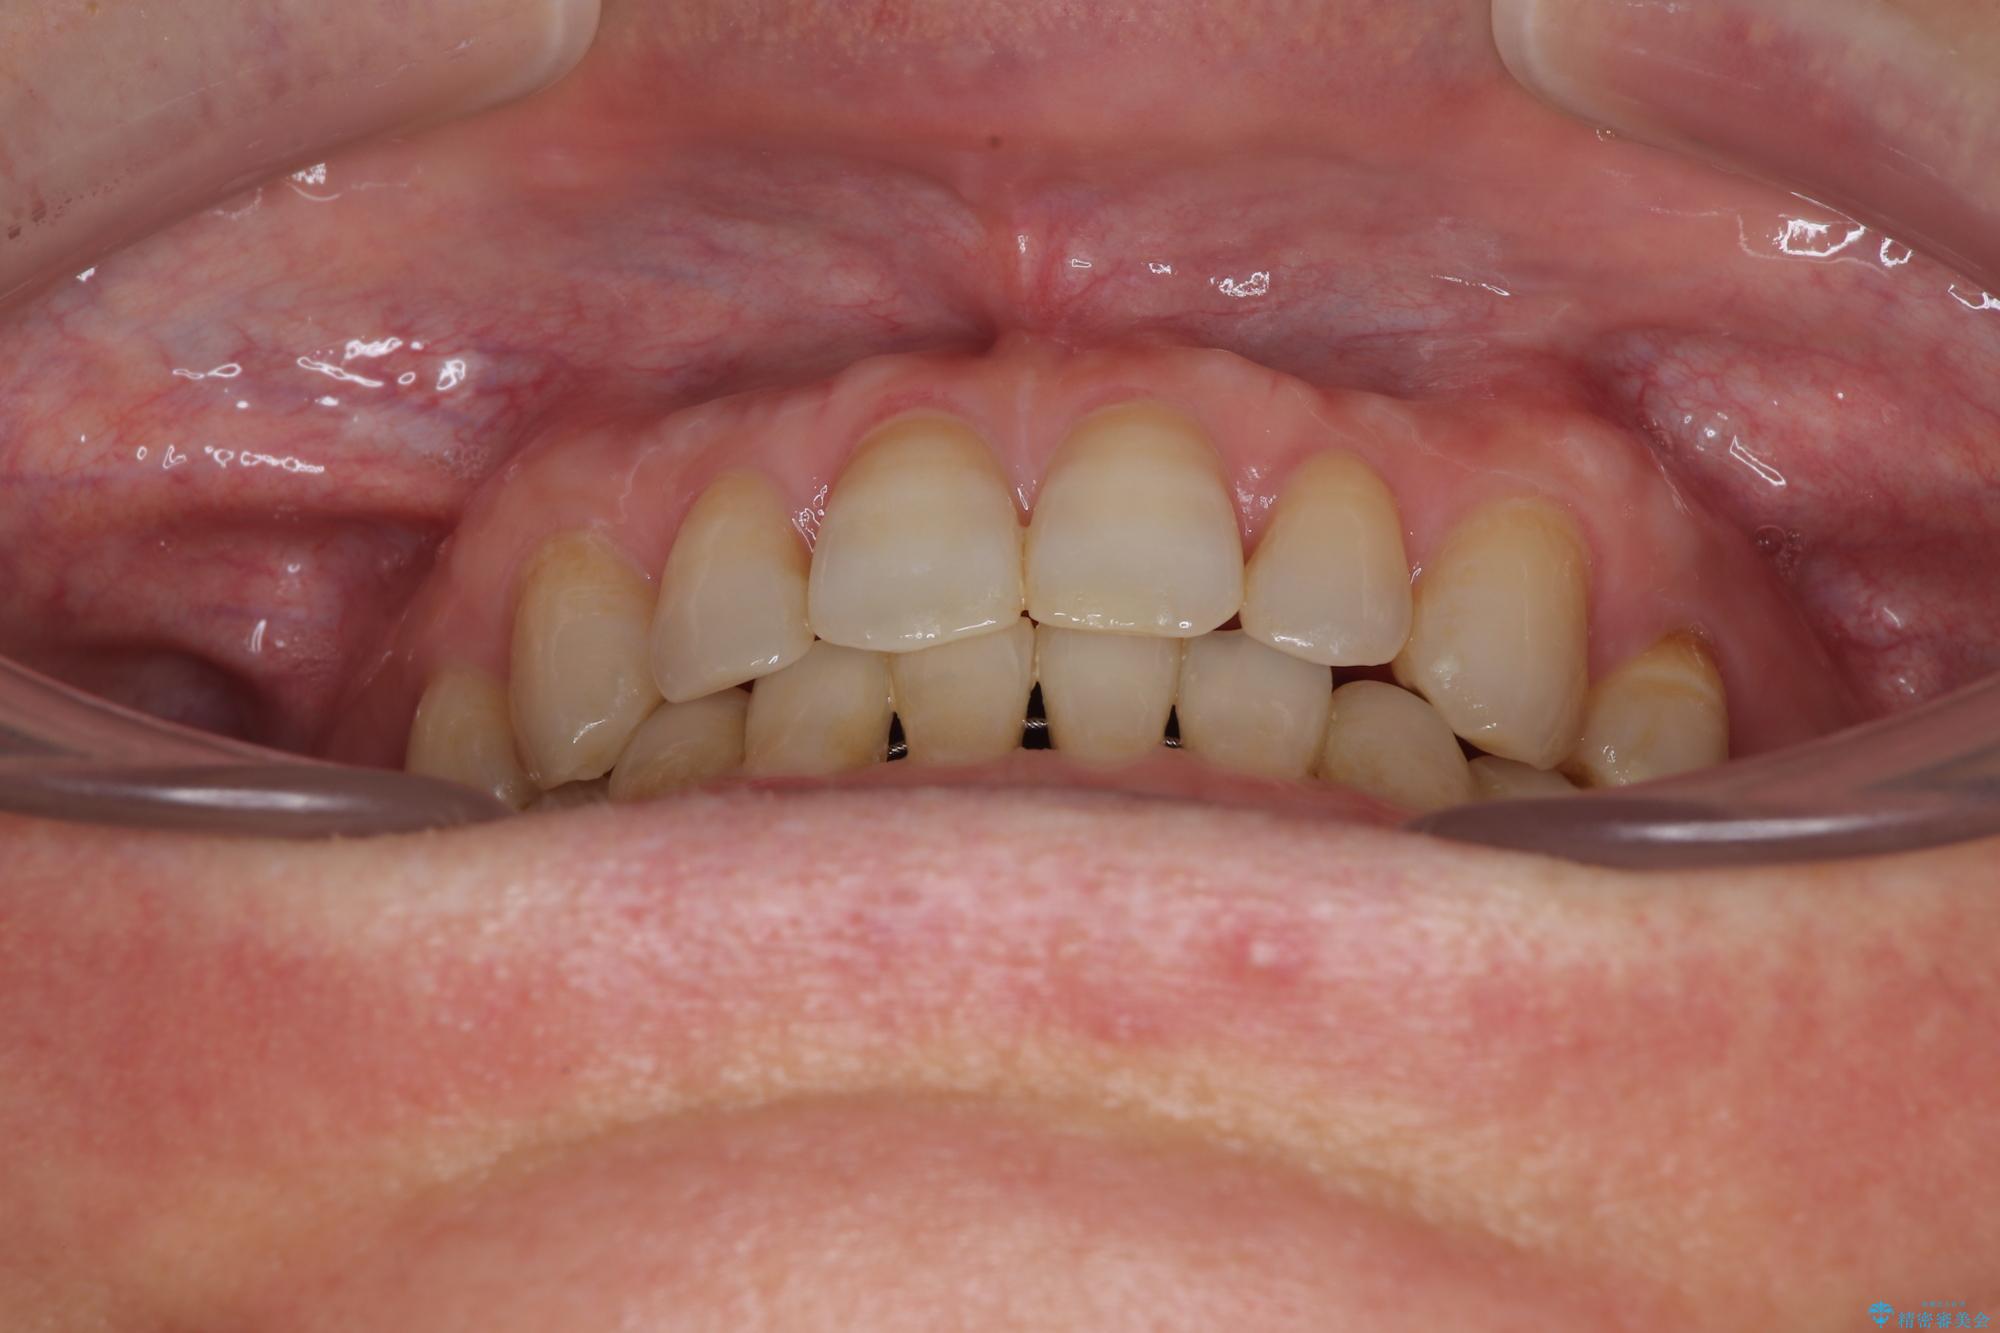

- 前歯のデコボコと隙間の空いた歯列を気にして来院された患者様です。

下顎前歯が隠れるほどのディープバイトにより、強い咬合力と突き上げで上顎歯列に隙間が空いている状態でした。

手前に傾斜している奥歯をワイヤー装置で立ち上がらせ、咬み合わせの高さを挙上することで突き上げを解消し、空隙歯列を改善していくこととしました。

ディープバイトが改善され、睡眠時の食いしばりも緩和され、顎への負担が軽減されました。